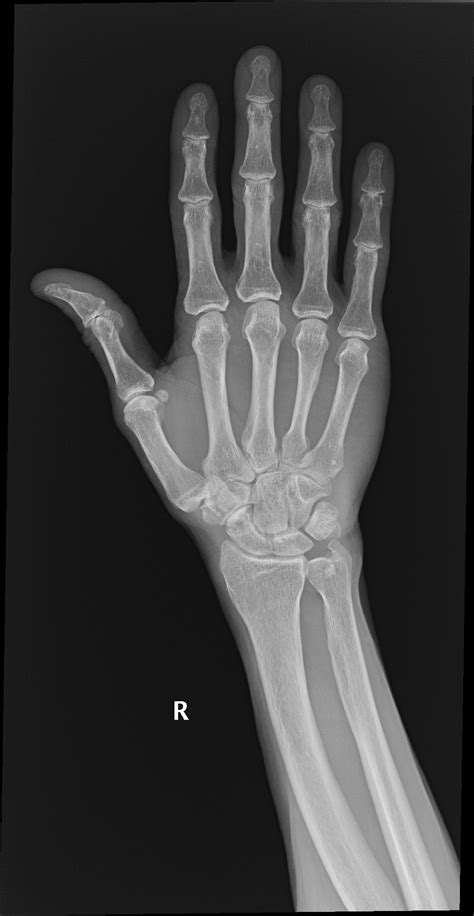

Diagnosing a fractured triquetral bone involves a combination of physical examination and imaging tests. The diagnostic process typically includes:

• Physical examination: A healthcare provider will assess the wrist for swelling, tenderness, and range of motion.

• X-rays: Standard X-rays can often reveal a fracture in the triquetral bone. However, due to the small size of the bone, additional views or specialized imaging may be required.

• CT scan: A computed tomography (CT) scan provides detailed images of the bone and can help identify fractures that are not visible on standard X-rays.

• MRI: Magnetic resonance imaging (MRI) can be used to assess soft tissue injuries and provide a more comprehensive view of the wrist joint.

In some cases, a combination of these imaging tests may be necessary to confirm the diagnosis and determine the extent of the injury.